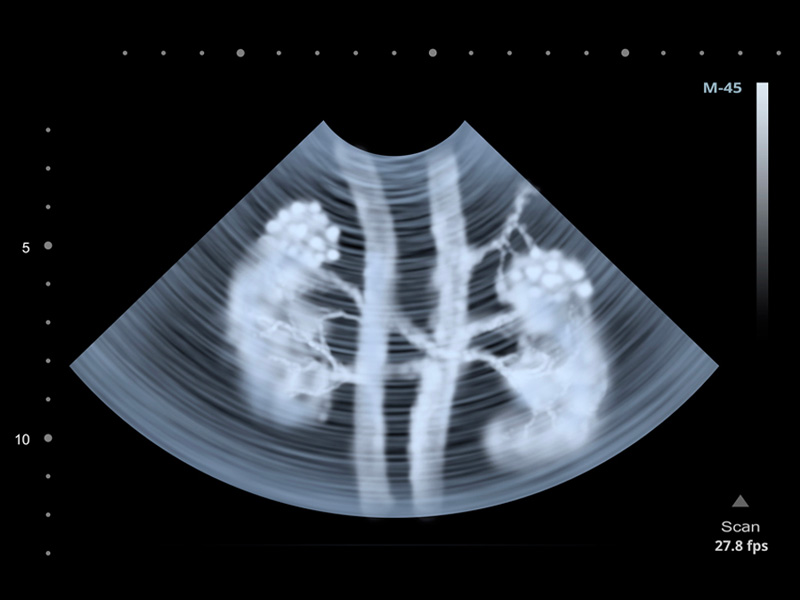

Ngoài ra, bạn cần phải nhịn tiểu để kết quả siêu âm sỏi thận được chuẩn xác. Việc này rất quan trọng giúp xác định được vị trí sỏi thận và kích thước sỏi thận bao nhiêu.

Kết quả siêu âm sỏi thận giúp cho việc phẫu thuật được chuẩn xác hơn